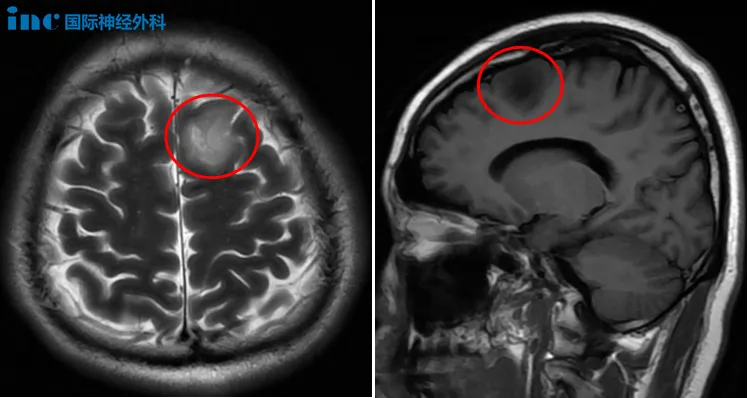

申先生刚过而立之年,有一个幸福的家庭,但这一切却险些被一个偶然打破。一次常规的体检,申先生被告知存在“颅内占位性病变”。可自己的身体一向健康,并没有任何不适。为了确诊,他与妻子一同前往医院,头颅核磁显示,他的左侧额叶确实可以看到一个大小约27×23mm的病灶,考虑为低级别胶质瘤。

两天后,进一步的头颅MRS检查也证实了这一结果。申先生一家顿时陷入泥潭之中,可要想从泥潭中干干净净地出来绝非易事,于是,一家人开始在各种渠道中寻找治疗的方法。